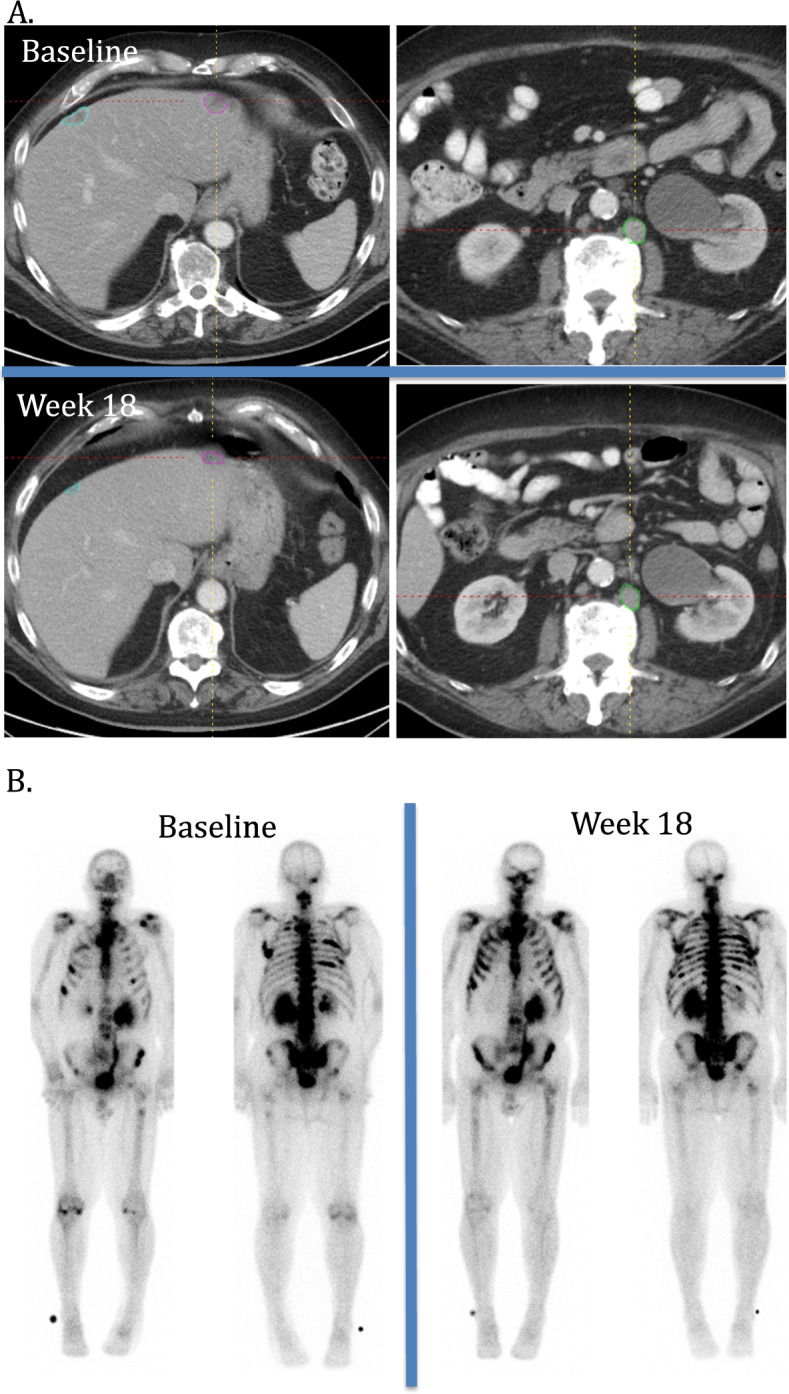

Metastatic prostate cancer is known to have high inter- and intra- patient tumor heterogeneity with respect to site, that may impact treatment outcome [22–24]. There is both heterogeneity at baseline as well as during follow up with respect to site of progressive disease and new lesion development. Therefore, multimodality imaging to separately assess soft tissue disease and bone disease is usually combined to provide a single response to therapy (Fig. 4) [3, 24]. In our study the presence of visceral disease at baseline was associated with an increased risk of disease progression by either RECIST or bone scan assessment and a shorter time to progression. As a cause of disease progression, soft tissue progression was seen in both those with and without visceral involvement at baseline. New lesions occurred in 50% (11/22) and 73% (22/30) of these patients with and without visceral involvement, respectively. Of those patients with pre-treatment visceral disease, progression due to presence of new lesions was associated with a significantly longer time to progression (3.1 months (2.8–4.3 months) than those with worsening of pre-existing lesions (1.8 months (1.6–2.7 months; p = 0.044).

Fig. 4.

Example case: Baseline visceral disease with worsening disease by BSLA bone scan only as source of disease progression. A. Axial CT of the abdomen at baseline and week 18. Soft tissue target lesions at baseline include liver (blue and pink circles) and retroperitoneal lymph node (green circle) and were stable and slightly smaller at week 18. B. AP and PA Tc-99 bone scans were also performed at baseline and week 18. Multiple bone lesions are present at baseline, with increased and new lesions involving ribs bilaterally and right pelvis at week 18